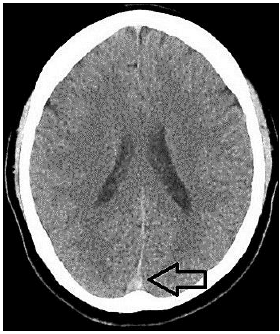

“Paciente, sexo feminino, 40 anos de idade, tabagista ativa, teve quadro de Covid-19 leve há uma semana, evoluindo com cefaleia holocraniana persistente, de forte intensidade, refratária à analgesia simples. Nega ter cefaleia prévia. Após três dias de dor, cursou com um episódio de crise convulsiva generalizada, sendo, então, levada ao hospital de referência próximo a sua residência, onde realizou a seguinte tomografia computadorizada de crânio sem contraste:”

De acordo com as informações, a indicação na tomografia computadorizada de crânio sem contraste se refere ao seguinte sinal radiológico: